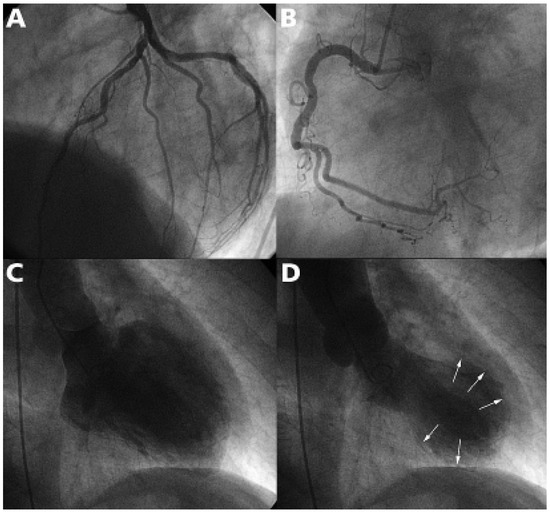

While substantial progress has been made over the past decade in the medical treatment of heart failure, certain patients fail to respond to optimal treatment despite the availability of excellent drugs. Cardiac resynchronisation therapy, or multisit...